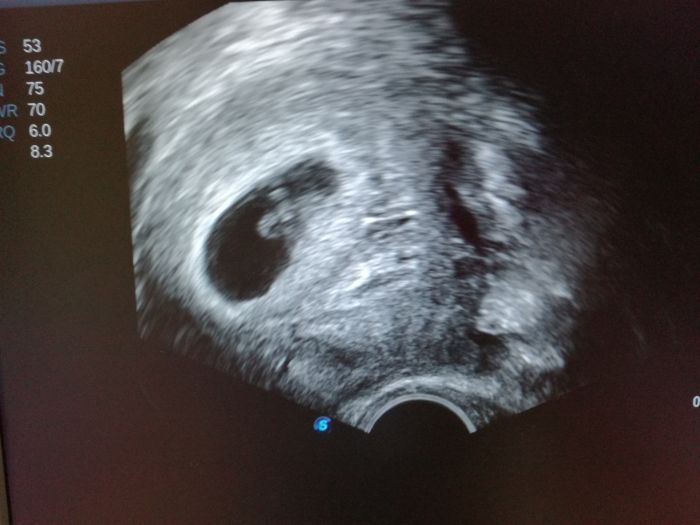

[1005717]

My byli v Usti dneska

Tak my jsme dneska po velkem utz a bude to dalsi KLUUUK ?